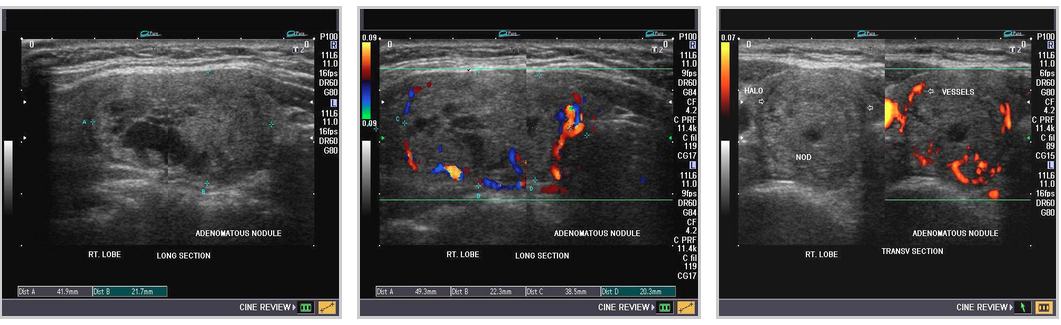

ADENOMAS

thyroid_adenomatous nodules thyroid_follicular adenoma